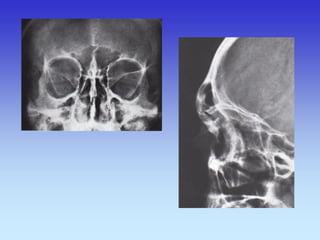

SINUSI PA snimka

1.Nosna pregrada

2.Frontalni sinus

3.Maksilarni sinus

4.Etmoidni sinus

PROFILNA SNIMKA GLAVE